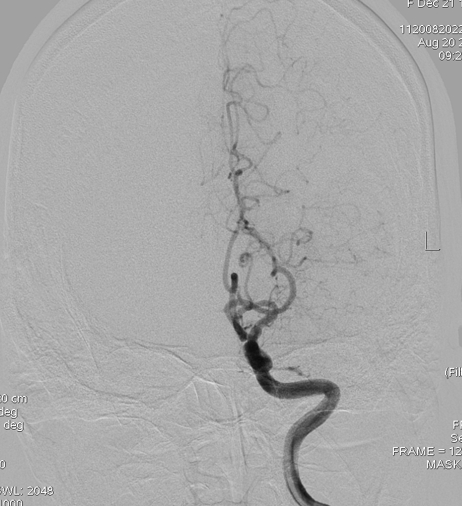

左侧大脑中动脉闭塞: